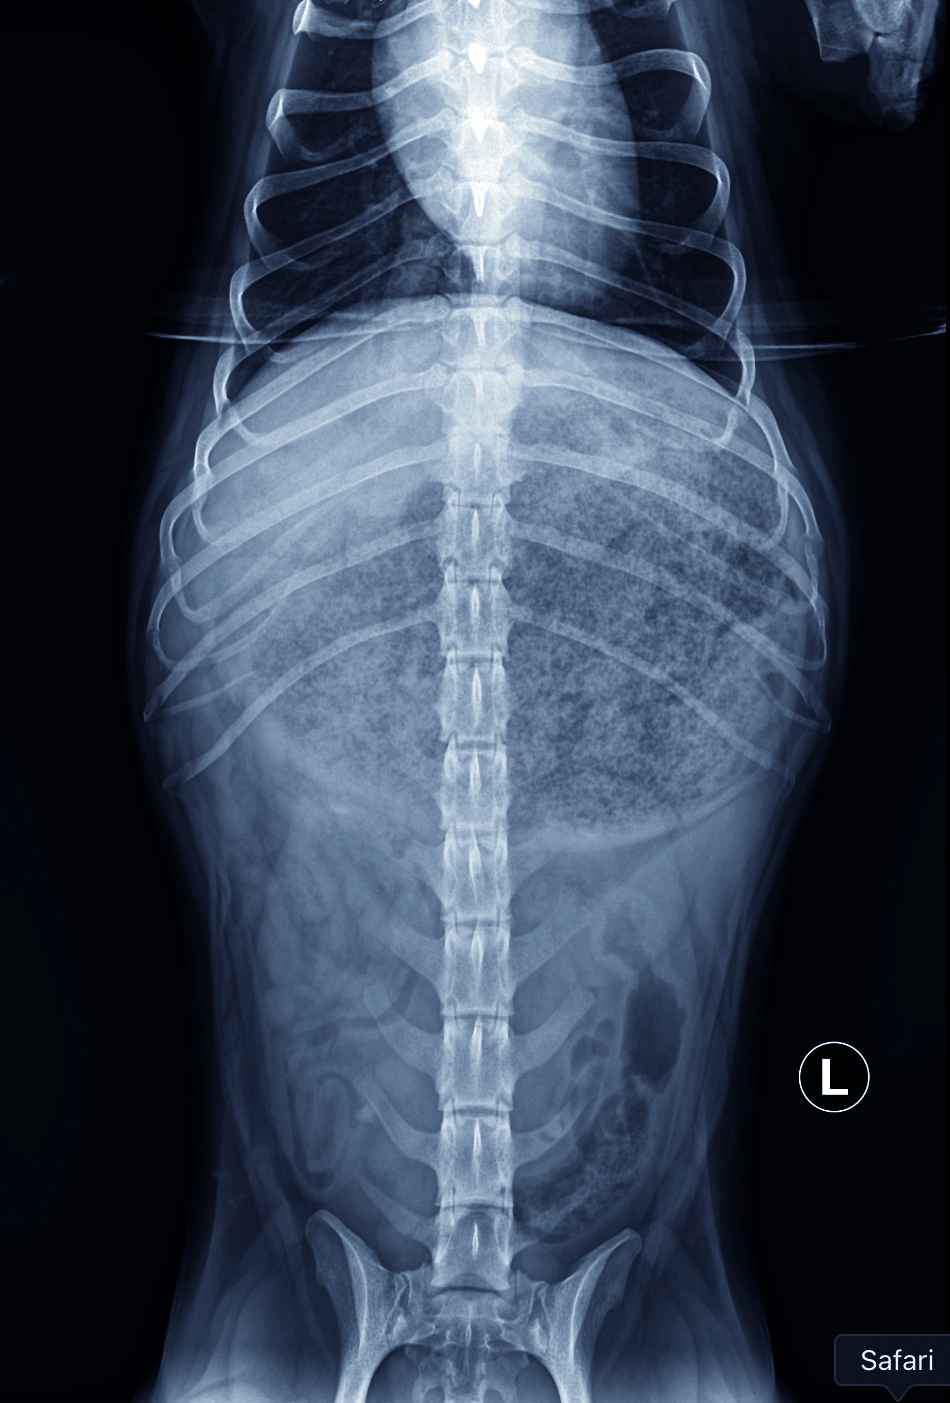

Des radiographies abdominales orthogonales (photos 1A et 1B) sont réalisées.

Les radiographies abdominales mettent en évidence une silhouette stomacale hétérogène distendue avec un pattern tacheté/moucheté en son sein, un effet de masse en région crâniale est observé (photo n° 2).

Associées aux antécédents cliniques, elles suggèrent la présence d'un cyano-bézoard gastrique, formé à la suite de l'ingestion de colle, entraînant une obstruction du pylore et du cardia.